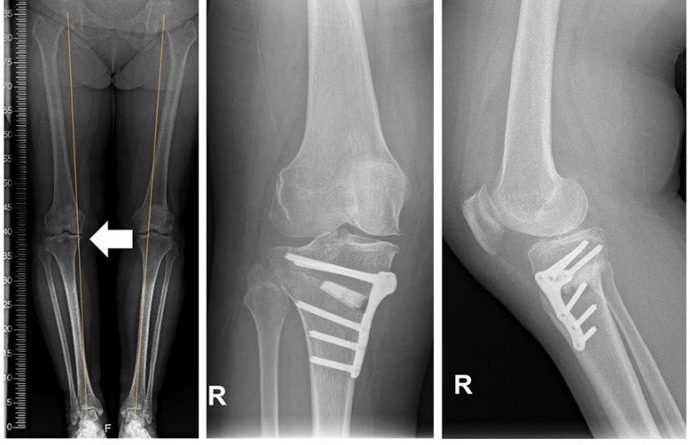

KOLJENA VAM PUCKETAJU I ŠKRIPE – PRVI ZNAK TEŠKE BOLESTI U ORGANIZMU: Dr Tanja otkrila o čemu se radi

Stariji ljudi koji čuju zvukove klikanja, pucketanja ili škljocanja u ili oko zglobova koljena imaju veću vjerovatnost da će razviti